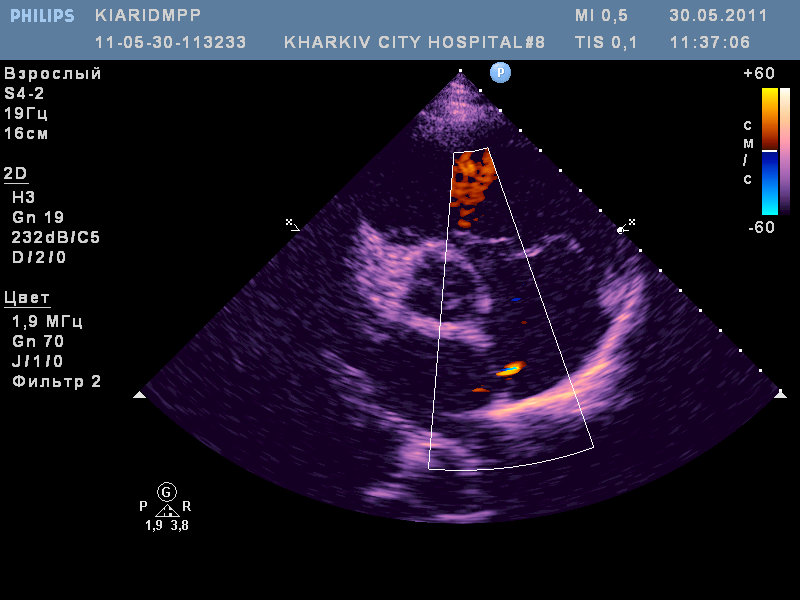

ВПС- высокий дефект межпредсердной перегородки (типа sinus venosus) с наличием аневризмы межпредсердной перегородки и сбросом слева-направо; сеть Киари.